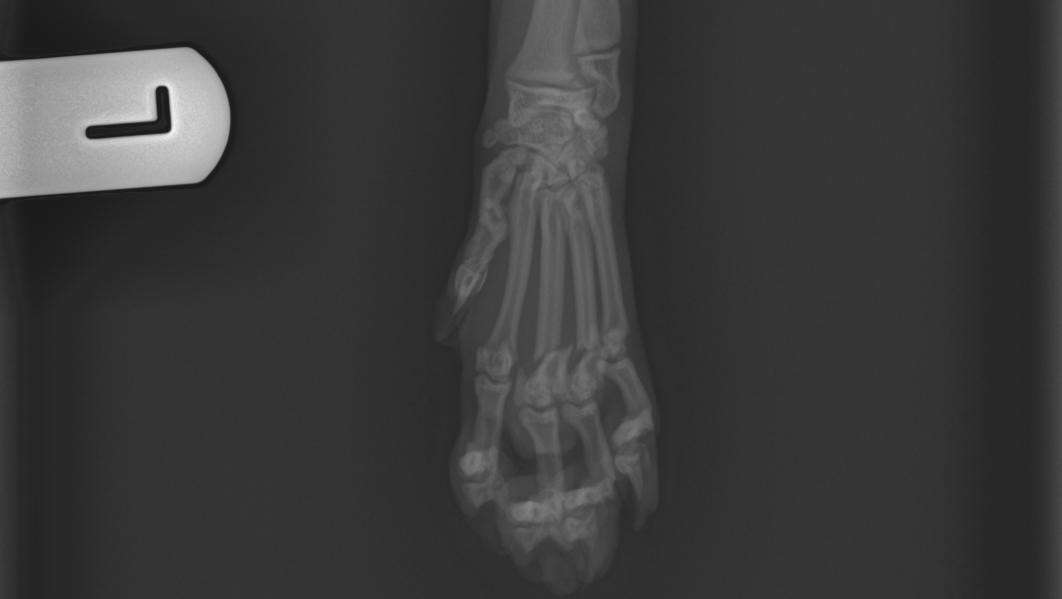

Levamo-lo de imediato ao veterinário, onde foi feita uma ecografia abdominal que, felizmente, não mostrou alterações internas. No entanto, o raio-x revelou fraturas, no rádio da pata dianteira direita e no metacarpo da pata dianteira esquerda.